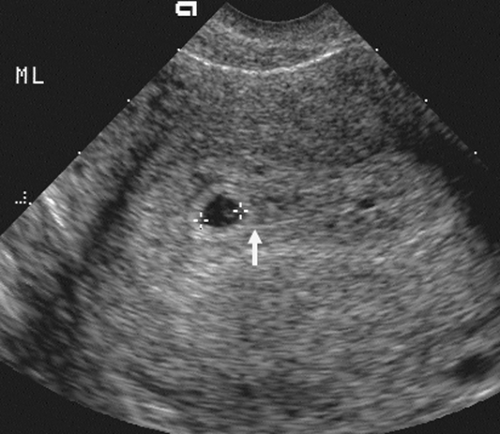

[Figure, Measurement of this gestational sac...] - StatPearls - NCBI

The Normal Gestational Sac